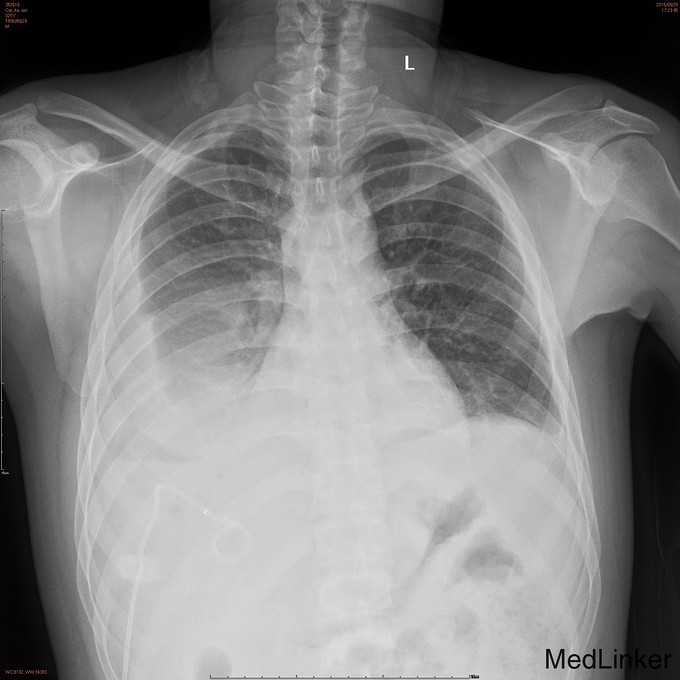

查体: 腹部平软,右下腹及右上腹可见两条引流管,引流出棕色臭味脓液,右下腹有压痛、反跳痛,余腹无压痛及反跳痛。 辅查: 1.腹部CT:1.原阑尾炎穿孔并周围及腹盆腔多发包裹性脓肿形成治疗后复查,现累及范围如上述,与前对比盆腹腔多发脓肿明显吸收变小。 2.腹膜炎;腹腔少量积液,与前对比减少。 3.双侧胸腔积液,与前对比减少;双肺下叶节段性肺不张,较前复张。 4.肝多发小囊肿。 2.胸片:1.右侧胸腔中量积液,左侧胸腔少量积液。 2.双下肺炎症及肺压缩性不张。 3.腹腔引流液培养:大肠埃希菌;屎肠球菌(D群)。